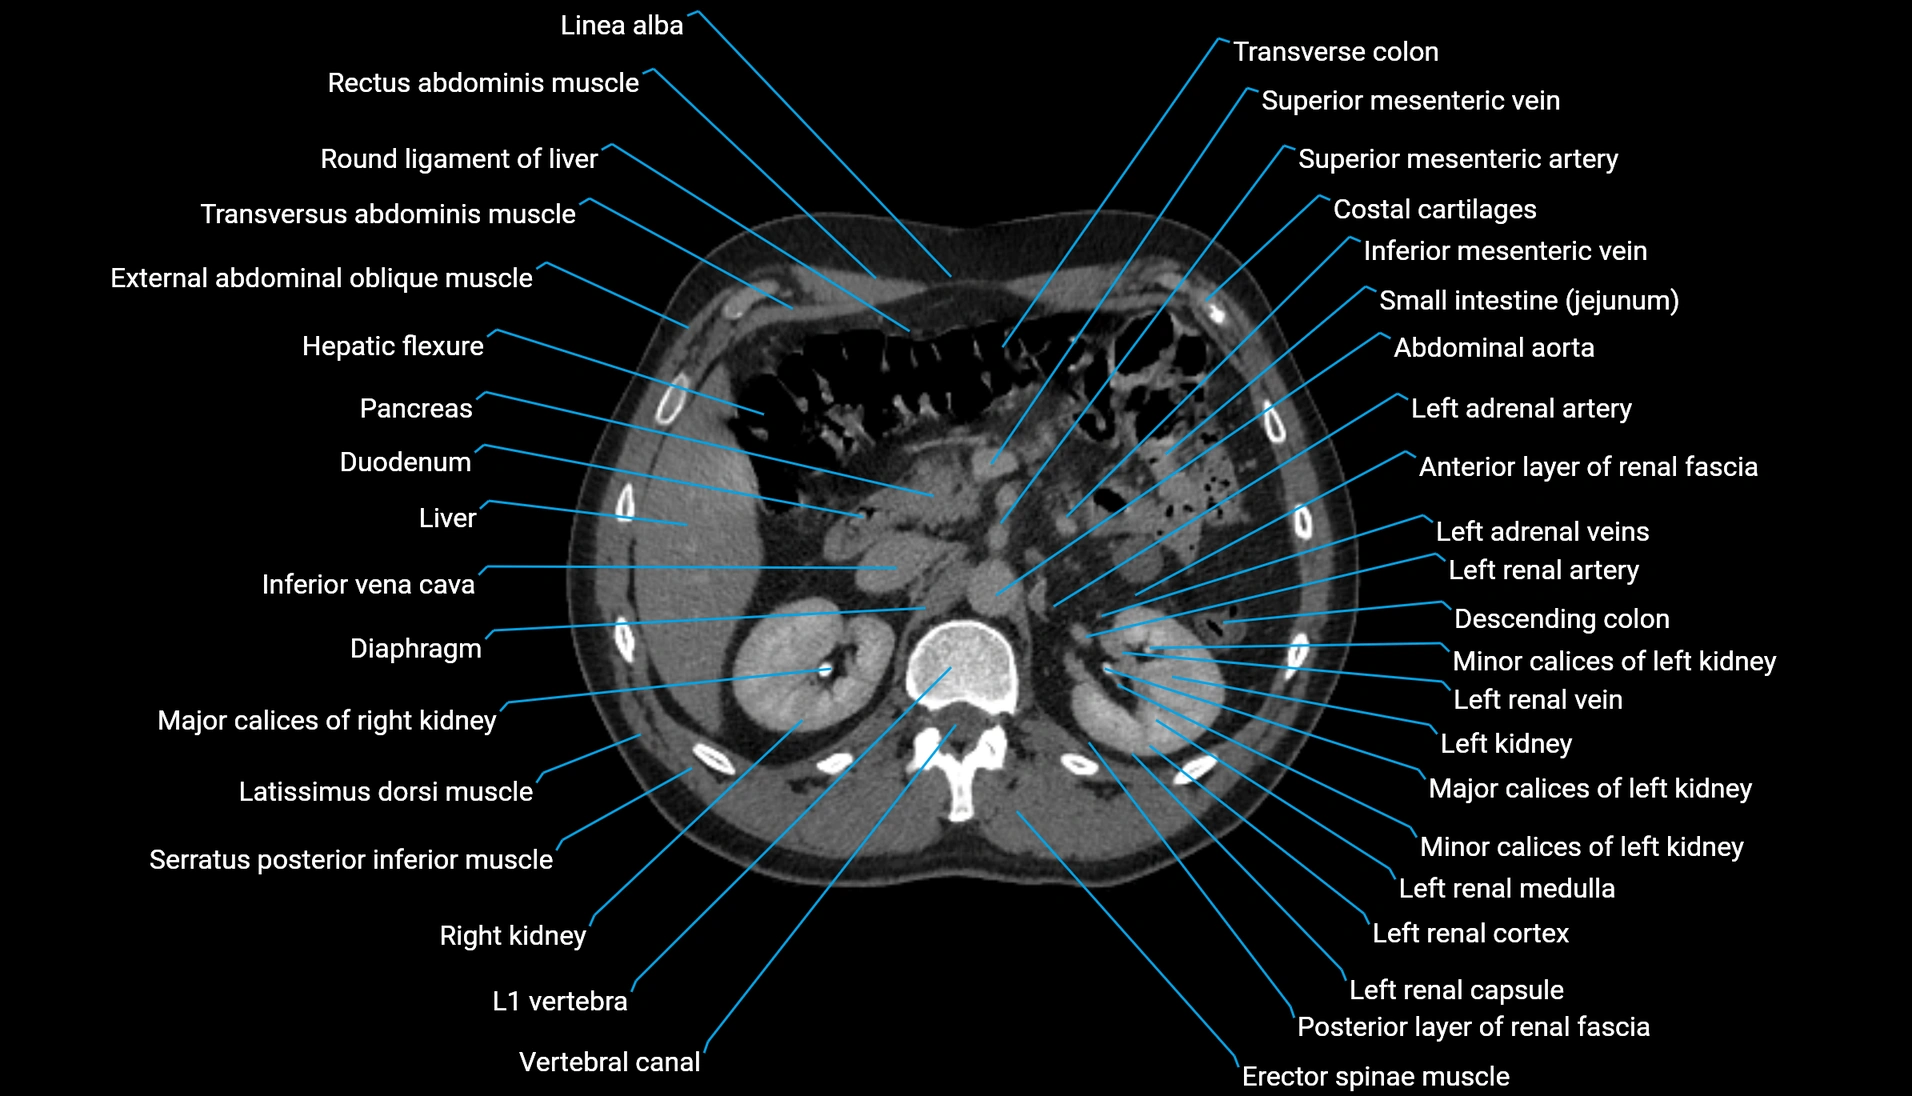

CT Appearance

Non-contrast CT:

-

Demonstrates cortical bone of acetabular rim in excellent detail

Detects fractures, dysplasia, retroversion, or bony overcoverage (pincer impingement)

3D reconstructions used in preoperative hip surgery planning

CT VRT 3D image

CT image